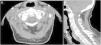

Cervico-occipital computed tomography (CT) demonstrated deposition of calcium pyrophosphate dihydrate crystals around the odontoid process of axis in a 87-year-old female patient with initial diagnosis of polymyalgia rheumatica (Fig. 1A, B). Patient had an acute severe cervico-occipital pain and markable neck stiffness. The patient had no shoulder or pelvic girdle pain and no jaw claudication. There is no history of trauma. There was a long personal history of knee pain due to calcium pyrophosphate dehydrate crystal deposition disease. Physical examination revealed limited passive cervical rotation without focal neurologic deficit. Laboratory results revealed elevation of erythrocyte sedimentation rate of 54mm/h and a normal C-reactive protein (5mg/dL). A knee radiography confirmed peripheral calcium pyrophosphate deposition disease. CT images showed atlantoaxial synovial calcifications in a crown around the odontoid process. A diagnosis of crowned dens syndrome (CDS) or periodontoid calcium pyrophosphate dehydrate crystal deposition disease was made. The patient was improved with a combination of prednisolone and nonsteroidal anti-inflammatory drug (NSAID) in a week. CDS is a rare clinical and radiological entity described firstly in 1985 and which pathophysiologic is not completely clear.1 This condition is accompanied by acute cervico-occipital pain and stiffness with severe limitation of neck rotation.2 The elevation of inflammatory markers is common.3 CDS can be misdiagnosed as various rheumatic diseases namely rheumatoid arthritis, spondyloarthritis, giant cell arthritis and PMR, as in our case.4,5 For diagnosis, cervico-occipital CT, showing calcification around the odontoid process, is the gold standard and should be done as soon as symptoms appear.6 Patients respond well to corticosteroids, NSAIDs and colchicine.6 Surgical procedure is performed rarely. CDS is a rare disease entity with various differential diagnosis. Thus, a high index of clinical suspicion is needed to obtain an early accurate diagnosis avoiding unnecessary exams or treatments.